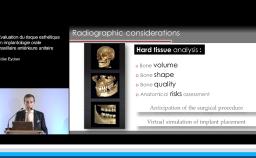

A partir de la description des facteurs de risque esthétique du bloc incisivo-canin maxillaire, de la présence d’os et de gencive autour des implants, le conférencier présente une succession de cas cliniques décrivant ses procédures chirurgicales et prothétiques.

- de déterminer le bon timing de chirurgie implantaire post extractionnelle

- de réfléchir sur la préservation à moyen-long terme de l’os autour des implants